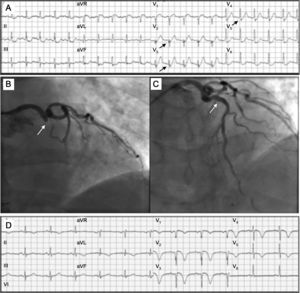

El segundo caso es un varón de 65 años sin antecedentes de interés, atendido por dolor torácico súbito. El primer ECG (figura 2A) muestra de nuevo descenso del segmento ST de hasta 3mm a expensas del punto J, con mínima Q, pérdida de onda R y ondas T prominentes en derivaciones precordiales (sobre todo V2-V3). Existe en este caso ascenso del segmento ST en aVR de hasta 1,5mm, Q en aVL y descenso del ST en derivaciones inferiores, que alcanza 2mm en II. La coronariografía urgente mostró la oclusión trombótica de la arteria descendente anterior proximal (figura 2B) sin relleno colateral distal, que se trató con angioplastia e implante de stent farmacoactivo (figura 2C). El ECG tras el procedimiento (figura 2D) muestra de nuevo los hallazgos típicos del infarto anterior en evolución.

A: electrocardiograma a los 120min de iniciarse el dolor, con «complejos de De Winter» V2-V5 (flechas). B: oclusión de la descendente anterior proximal (flecha). C: restauración del flujo en la descendente anterior tras angioplastia e implante de stent (flecha). D: electrocardiograma tras el procedimiento; imagen de infarto anterior en evolución, con ondas Q en V1-V3, mínimo ascenso del ST y negativización de la onda T en V1-V5.